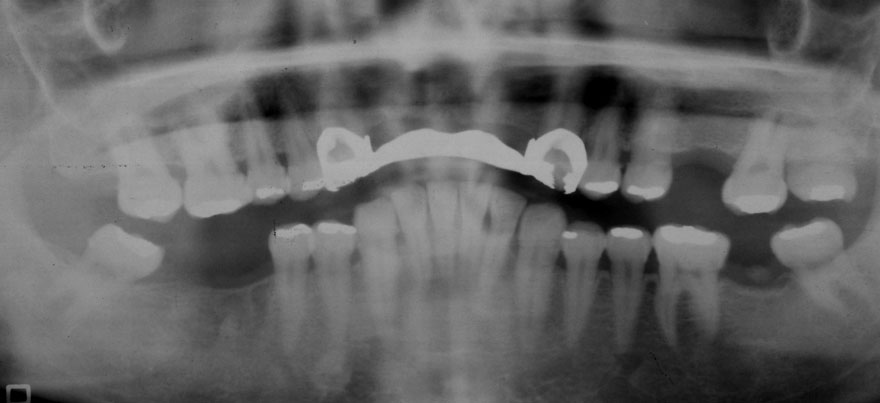

開始年齢 40代

初診時 40歳 女性 平均歯槽骨喪失量:3.14mm

32年後 72歳

平均歯槽骨喪失量:3.22mm

32年間喪失量:-0.08mm

年間喪失速度:-0.002mm

(ケア頻度:1.86ヵ月ごと)